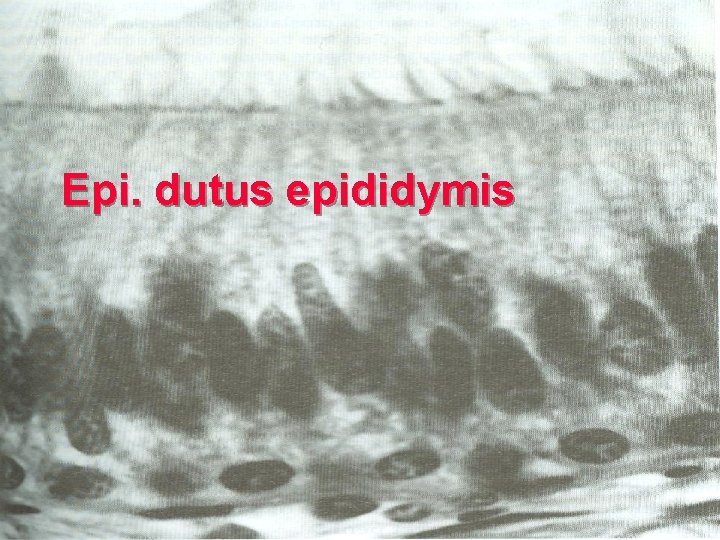

2. dutus epididymis l 4 -6 m,highly convoluted l pseudostratified ciliated columnar Epi. =principal C + basal C l lumen is regular,filled with sperm & secretions l the proximal , efferent ductules; the distal, ductus deferens.

Epi. dutus epididymis